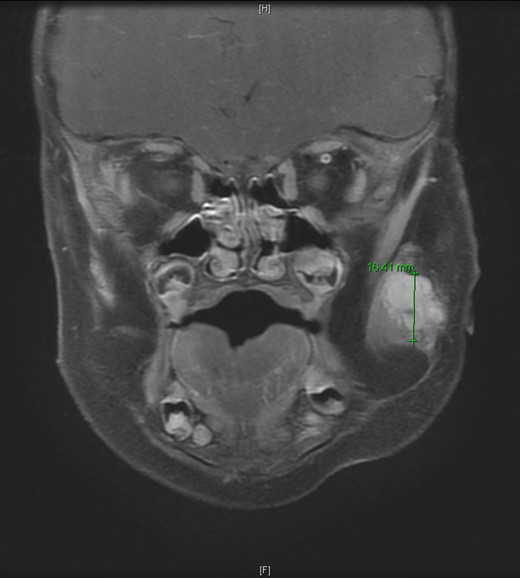

An 11-month-old male with a history of nasolacrimal duct stenosis and 4 mm thyroglossal duct cyst presented for evaluation of left facial swelling for 9 months. Approximately 6 months prior to admission, a mass was identified on the left cheek which had progressively increased in size over the past 2 months. The patient also had intermittent fevers the week prior to admission but was otherwise healthy. Baseline labs, including platelets, were within normal limits. On exam, he was found to have a firm, mobile, non-tender mass just inferior to the left zygomatic arch. Ultrasound revealed a vascularized solid lesion measuring 12 mm × 15 mm × 16 mm limited to the superficial soft tissues. MRI showed a multi-lobular mass with increased T2 signal centered within the left masseter and infiltrating signal in surrounding subcutaneous tissue (Fig. 1). The patient subsequently underwent ultrasound-guided core biopsy. The initial pathological diagnosis was consistent with TA, showing fibrovascular tissue containing compact nests of variably sized and ill-defined vascular channels. Immunohistochemistry staining showed the endothelial cells to be diffusively reactive for CD34 and CD31, partially reactive for D2-40, and negative for GLUT-1. However, upon further review, KHE was favored given the solid and infiltrative components on MRI, normal overlying skin on exam, and location of the lesion within subcutaneous fat. Accordingly, low-dose daily aspirin was prescribed prophylactically to prevent KMP. An MRI 2 months later, along with serial ultrasound images in the ensuing 26 months, showed no further growth (Fig. 2). His parents noted intermittent painless changes in size that did not seem to be related to any stimulus and returned to baseline size within hours. Surgical intervention at 3 years old is anticipated.

T2-weighted MRI revealed a homogenously enhancing 13 mm × 11 mm × 16.4 mm mass with indistinct margins centered within the left masseter muscle and protruding into the subcutaneous tissues laterally.